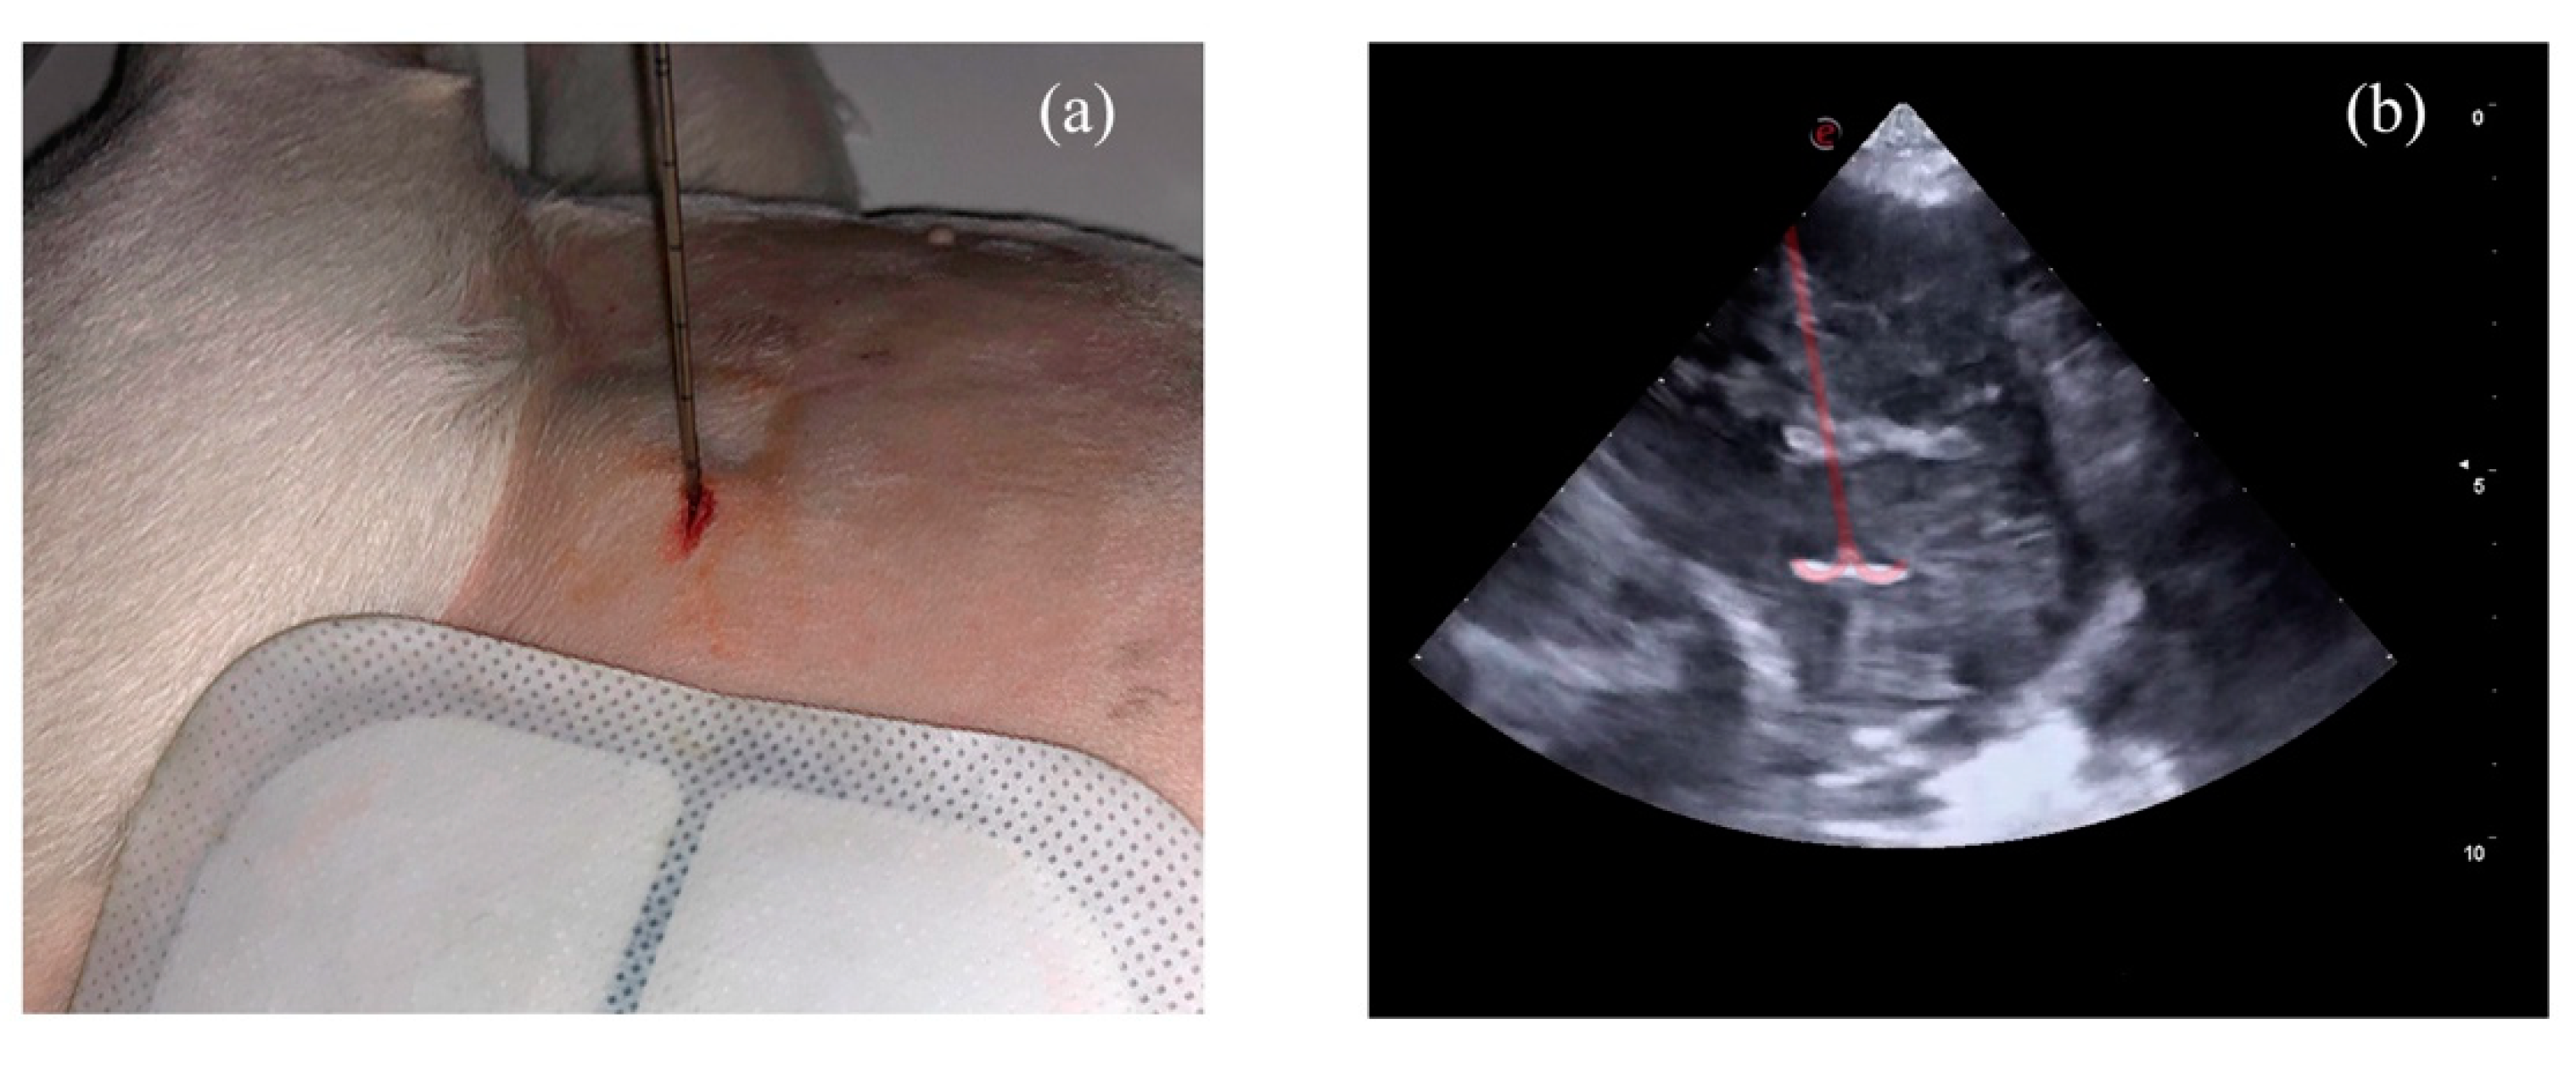

2. Materials and Methods